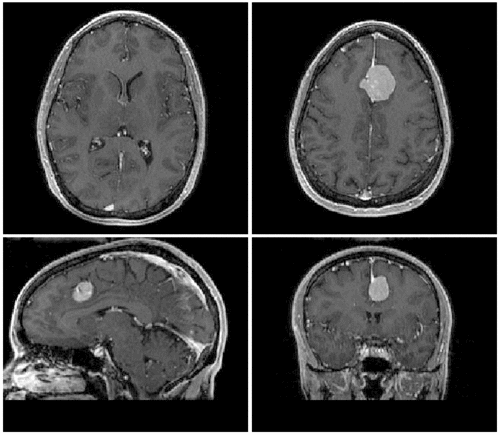

Slicer Registration Use Case Exampe #2: Inter-subject Brain MRI: axial T1 Tumor Growth Assessment

This is a classic case of change assessment. We want to know if the tumor changed since last exam.

MRI, brain, head, intra-subject, T1, tumor growth, meningioma, change assessment

reference/fixed : T1 SPGR , 0.9375 x 0.9375 x 1.4 mm voxel size, axial, RAS orientation.

moving: T1 SPGR , 0.9375 x 0.9375 x 1.2 mm voxel size, sagittal, RAS orientation.- Content preview: Have a quick look before downloading: Does your data look like this? Media:RegUC2_lightbox.png

| original orientation | |

| after registration |